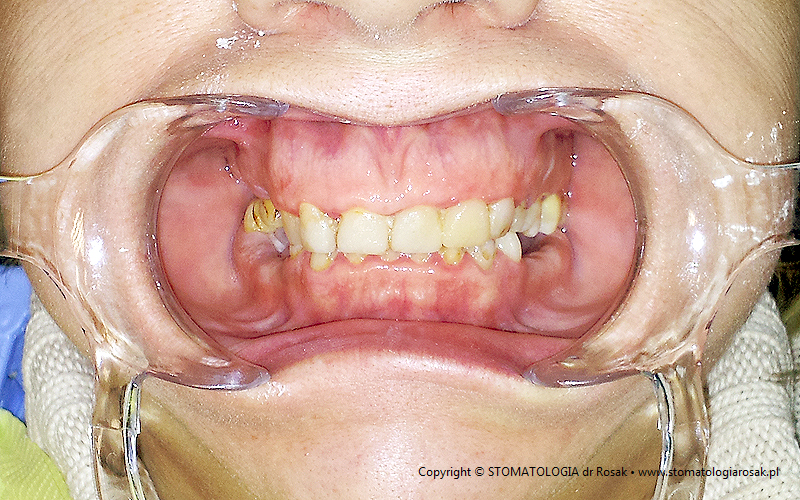

4. Pacjentka z nieestetycznymi wypełnieniami w odcinku przednim, z tzw. wysoką linią uśmiechu

(bardzo widoczne dziąsła) - przed leczeniem.

| 4a. Pacjentka przed leczeniem |

4b. Gotowe korony pełnoceramiczne na zębach przednich

(od trójki do trójki) |

| 4c. Widok od strony brzegów siecznych |